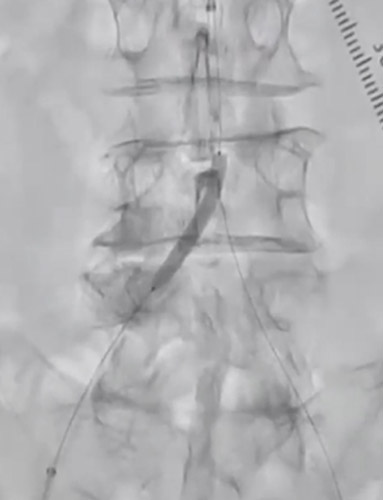

左dRAからエコーガイド穿刺を行いGlidesheateh Slender7FrとR2P SlenGuideの組み合わせでアプローチを開始した。その際、カバードステント(シャフト長135cm)の留置を予定していたため、よりガイディングカテのシステム全長を短くするためにR2P SlenGuideに止血弁を組み合わせた。R2P SlenGuideが病変部に対してコアキシャルになり難く、バックアップは十分に取れなかったが、6gワイヤー(0,014“)で病変を通過後、Navifocus WRでintra-plaque内であることを確認し、Senri 3-40mm でプレ拡張を行った(図3)(図4)。